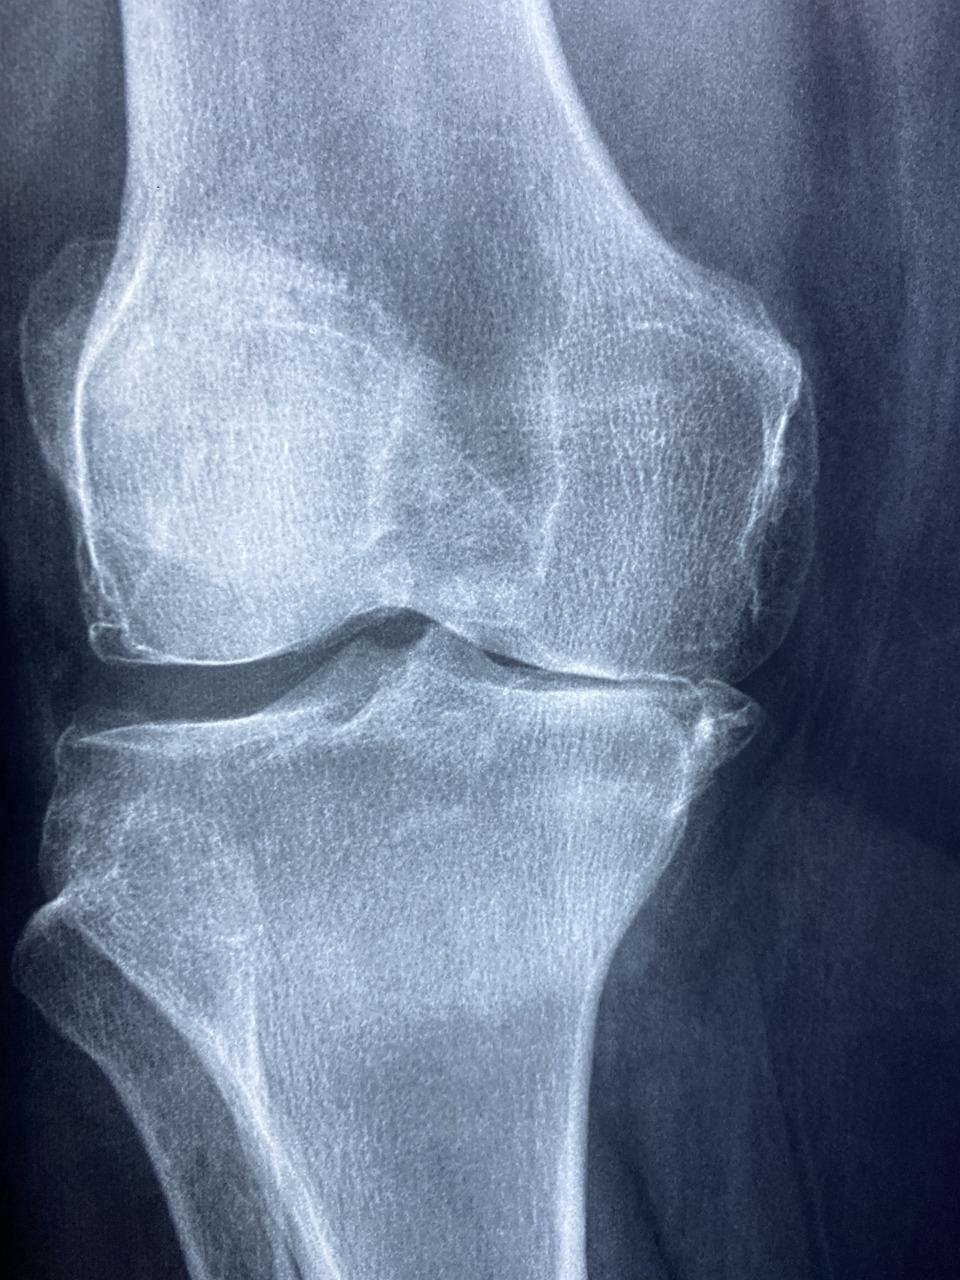

무릎 관절 부상도 매우 흔합니다. 러닝과 같은 반복적인 운동은 무릎 연골을 마모시키고 슬개건염(무릎힘줄염)과 같은 염증을 유발할 수 있습니다. 특히, 한국인들은 등산을 자주 즐기는데, 하산할 때 무릎에 가해지는 충격이 크므로 주의가 필요합니다.